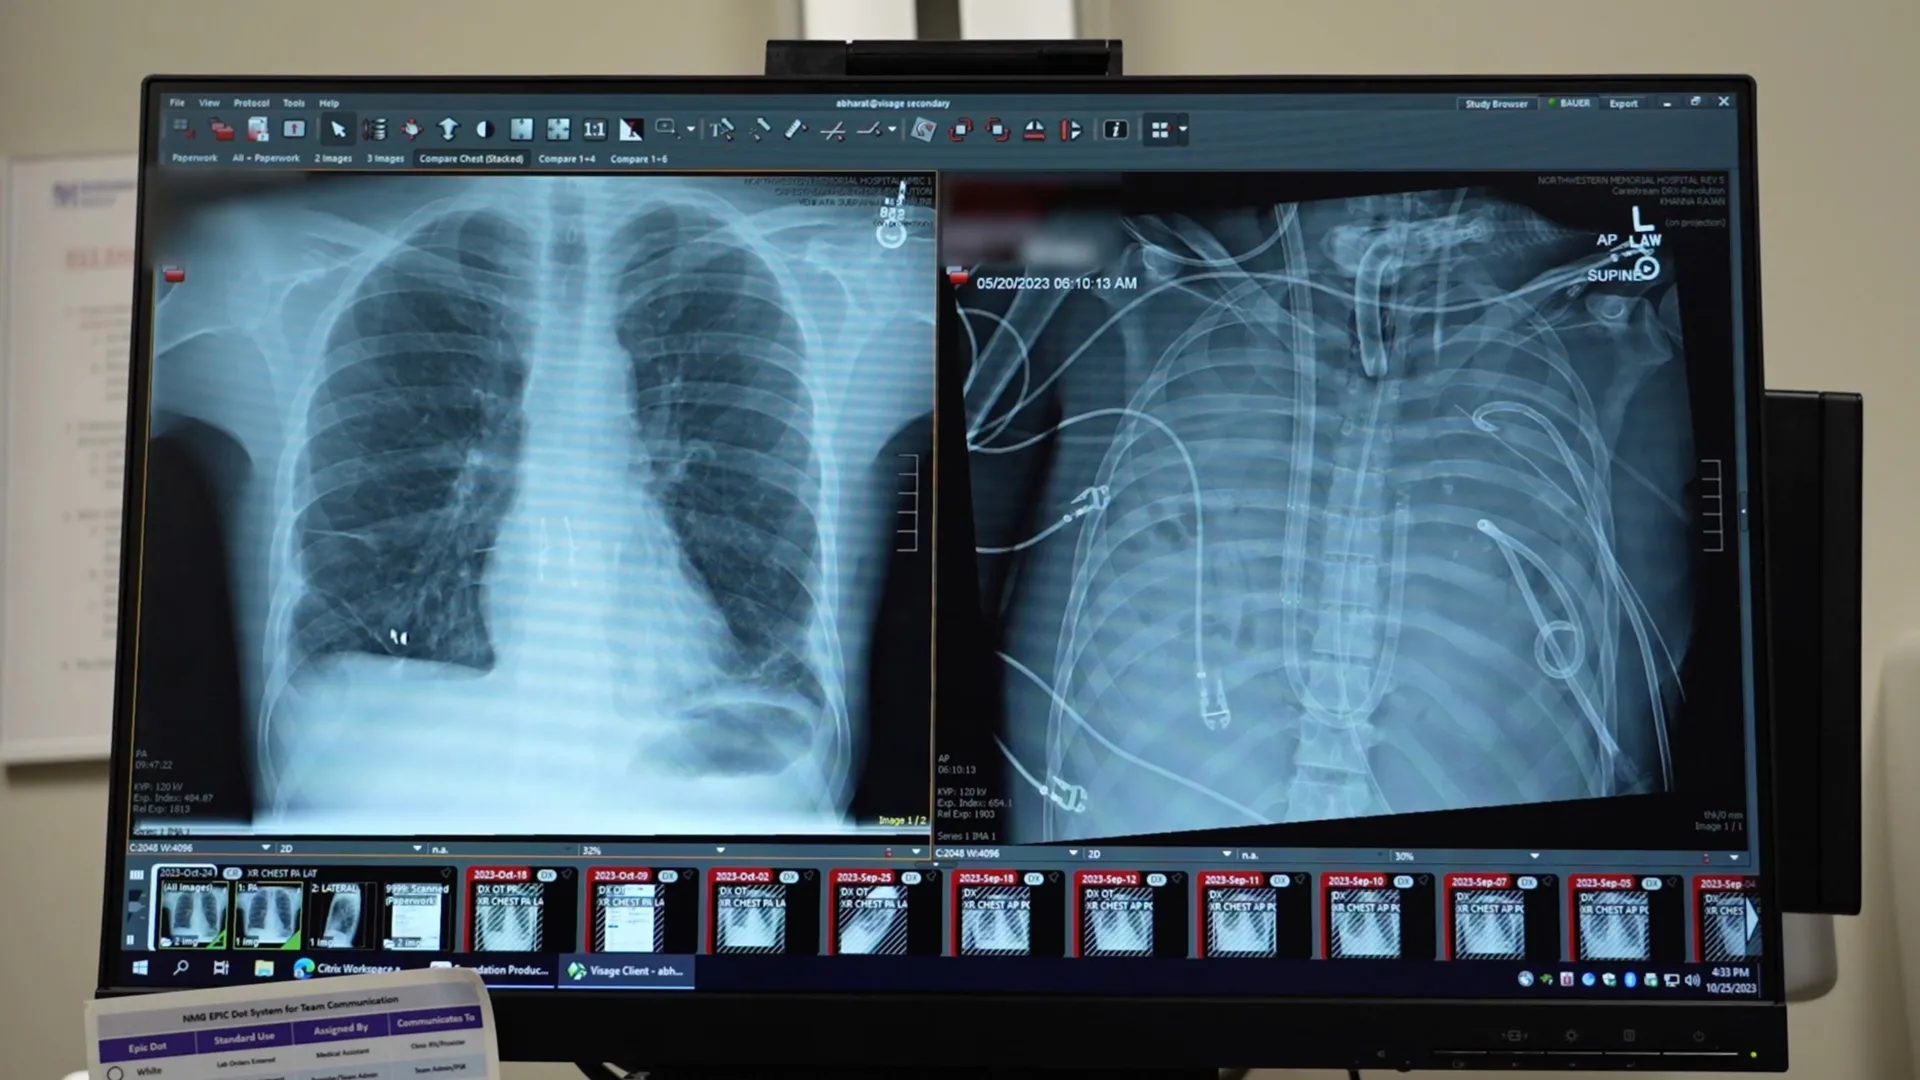

In a report published in the Cell Press journal Med, surgeons detail how they removed a man's severely infected lungs and used an "artificial lung" system to keep him alive until a double lung transplant could be performed. The case highlights a potential new way to keep critically ill patients alive while they wait for donor organs.

To address this, the medical team developed an artificial lung system designed to temporarily take over the lungs' role. This system oxygenated the blood, removed carbon dioxide, and supported circulation, allowing the heart and other organs to continue functioning even though the patient had no lungs.

After the damaged lungs were removed, the patient's condition began to improve. His blood pressure stabilized, his organs started recovering, and the infection came under control. Two days later, donor lungs became available, and surgeons successfully completed a double lung transplant. More than two years later, the patient is living a normal life with healthy lung function.